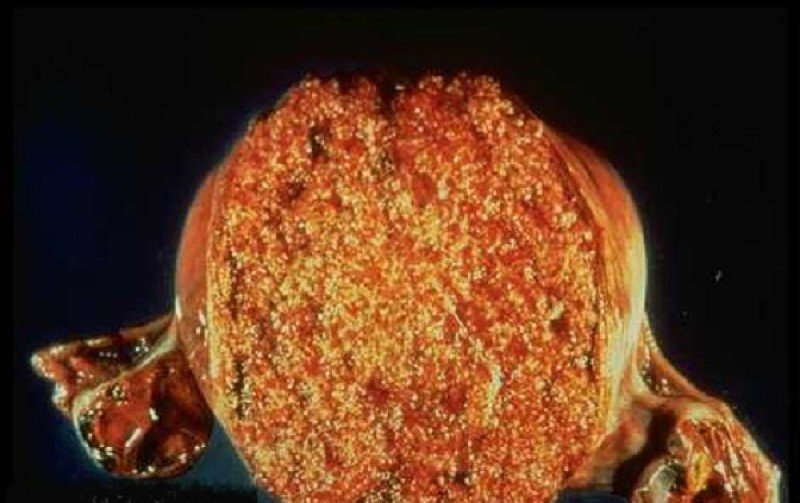

Медицина и диагностика: Инвазивный пузырный занос на УЗИ